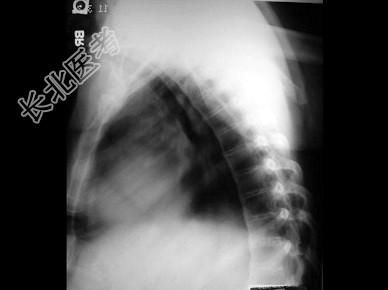

- 单项选择题男,21岁, 腰部不适,晨起加重半年余, X线检查如图,最可能的诊断是 ( )

A、类风湿关节炎

B、脊椎退行性变

C、强直性脊柱炎

D、化脓性脊柱炎

E、阻滞椎